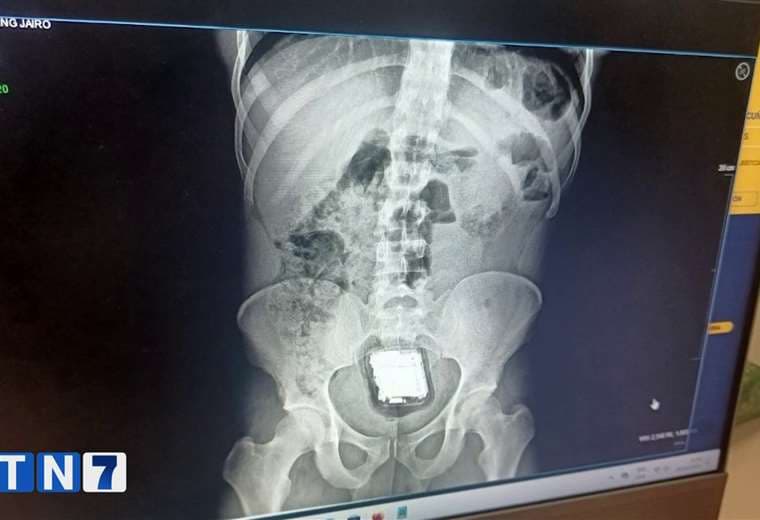

Una imagen muestra la radiografía tomada hace poco a un privado de libertad de La Reforma, en San Rafael de Alajuela, e ilustra la forma en que algunos de ellos son obligados a esconder los dispositivos electrónicos (ver nota de Telenoticias en el video adjunto).

Según el Ministerio de Justicia, en el 2023 y lo que va de este año han detectado a 78 reos del Complejo Terrazas que ocultaron en sus partes íntimas drogas, celulares, tarjetas SIM y cables de cargador, entre otros objetos. De esos 78, a 10 personas las llevaron a hospitales para extraerles los aparatos.